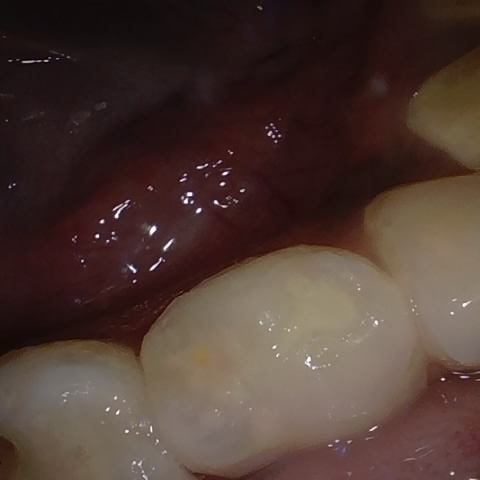

Incorrect Quality Level

The reference annotation for this image is

None

.

Please select the correct quality level.

Annotated as "Good"